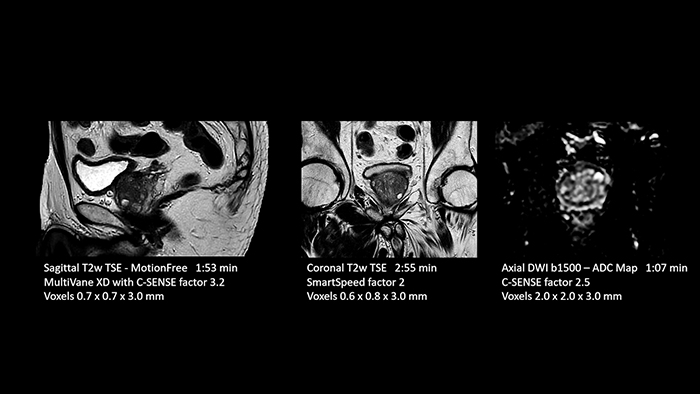

“Thanks to SmartSpeed, we are able to perform examinations extremely quickly. We can carry out most examinations in under ten minutes. Our MRI exam of the knee only takes six minutes. The shorter time makes it easier for patients to lay still, which helps prevent motion artifacts. Dr. Schröter also highlights their step forward in MRI of the prostate. “In prostate exams we have saved almost 50 percent of time. We used to need about 35 minutes for an MRI exam of the prostate and now we can do it in just 18 minutes with a significantly higher resolution and higher image quality.”

According to Dr. Schröter the advances that come with SmartSpeed enable them to more frequently use metal artifact suppression sequences, such as O-MAR, for imaging joints with prostheses. This sequence can now be acquired in the relatively short time of three minutes and Dr. Schröter observes significant progress in recognizing anatomy in the vicinity of the prostheses. SmartSpeed brought options for motion-free imaging, so motion artifacts no longer play a major role like before. Dr. Schröter says the team sees fewer repeat scans when using SmartSpeed, “Firstly, because patients’ time in the magnet is shorter, and secondly because SmartSpeed MotionFree reduces motion artifacts better than before.”

Dr. Schröter points out that a more confident diagnosis requires high-quality images with more diagnostic information. “Philips SmartSpeed provided that to us. AI denoises the clinical images without losing any important data, resulting in high-resolution images. It keeps all the information we need and makes the images better. We can apply SmartSpeed to almost all sequences. That is a big step forward! We use it for example in 3D imaging and in diffusion-weighted imaging, to dramatically reduce scan time or increase image resolution, which is quite useful. There are small lesions that we would certainly have seen without SmartSpeed, however it would have taken us longer to properly diagnose. In 3D MSK images with extremely high resolution, we uncover the finest anatomical structures and can thus report very detailed findings.”

- Prostate

With SmartSpeed also scan times for diffusion imaging and motion-free imaging can be reduced. Scanned without contrast agent. Performed with 1.5T Ambition X, dS Torso coil.

- Prostate

With SmartSpeed also scan times for diffusion imaging and motion-free imaging can be reduced. Scanned without contrast agent. Performed with 1.5T Ambition X, dS Torso coil.